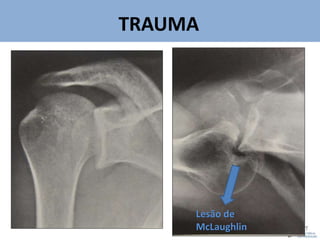

Lesão de

McLaughlin

50. Na luxação posterior do ombro, a lesão ântero-medial da

cabeça do úmero é conhecida como

A) BANKART.

B) HILL-SACHS.

C) McLAUGHLIN.

D) NEER.